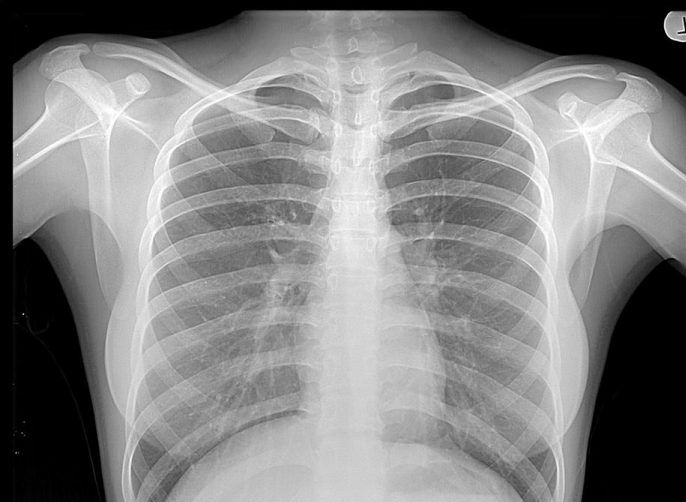

Radiatiile X sunt o forma de radiatii prin ionizare. Acestea pot fi foarte periculoase. Cel mai important lucru este sa se cunoasca modul in care actioneaza fasciculul incident de raze x. Exista mai multe caracteristici ale razelor x care fac din acest tip de radiatii unele deosebit de periculoase pentru utilizarea lor in laborator. Este important faptul ca razele x sa nu fie utilizate in mod abuziv pe parcursul vietii unei persoane, intrucat aceasta poate fi expusa la o cantitate mare de radiatii, cumulative, scrie sfatulmedicului.ro.

Razele x sunt un tip de energie electromagnetica. Acesta au lungimi scurte de unda, ceea ce le permite sa transporte destul de multa energie. Atunci cand acestea sunt interceptate de organismul uman intra si radiatiile ionizate in ecuatie. Radiatiile ionizate pot respinde electronii care orbiteaza in jurul nucleelor atomilor. Cand electronii se deplaseaza, acestia creaza grupuri de atomi numite ioni, care pot imprastia alti atomi prin celule celui expus la radiatii x.

Deteriorarea celulelor in urma radiatiilor poate modifica ADN-ul si duce la cresterea sanselor formarii celulelor anormale in timpul replicarii sau chiar a transformarii in celule canceroase, in timp. Acesta este motivul pentru care specialistii utilizeaza doar doza necesara de radiatii x sau cea mai mica doza, in cazul imagisticii medicale.

Mai mult, radiatiile se acumuleaza in timp, astfel incat pot sa apara probleme si in cazul in care se fac investigatii cu raze x in mod frecvent. Razele x nu sunt doar nocive, totusi. Din fericire celulele umane se pot vindeca in urma expunerii de scurta durata la raze x. In cazul unor afectiuni, razele x pot oferi imaginea unor portiuni de dinti sau organe interne care nu sutn vizibile din exteriorul corpului.

Acestea ajuta la evaluarea fracturilor, rupturilor sau modificarilor anormale ale oaselor si permit medicilor sa urmareasca eficienta operatiilor chirurgicale. In cele din urma, beneficiile stabilirii diagnosticului adecvat si a urmarii tratamentului optim sunt de multe ori mai mari decat riscurile presupuse de radiatii. Este adevarat ca razele x pot oferi chiar si indicii in cazul situatiilor mai delicate, cum ar fi cazul in care un copil inghite in mod accidental un obiect.